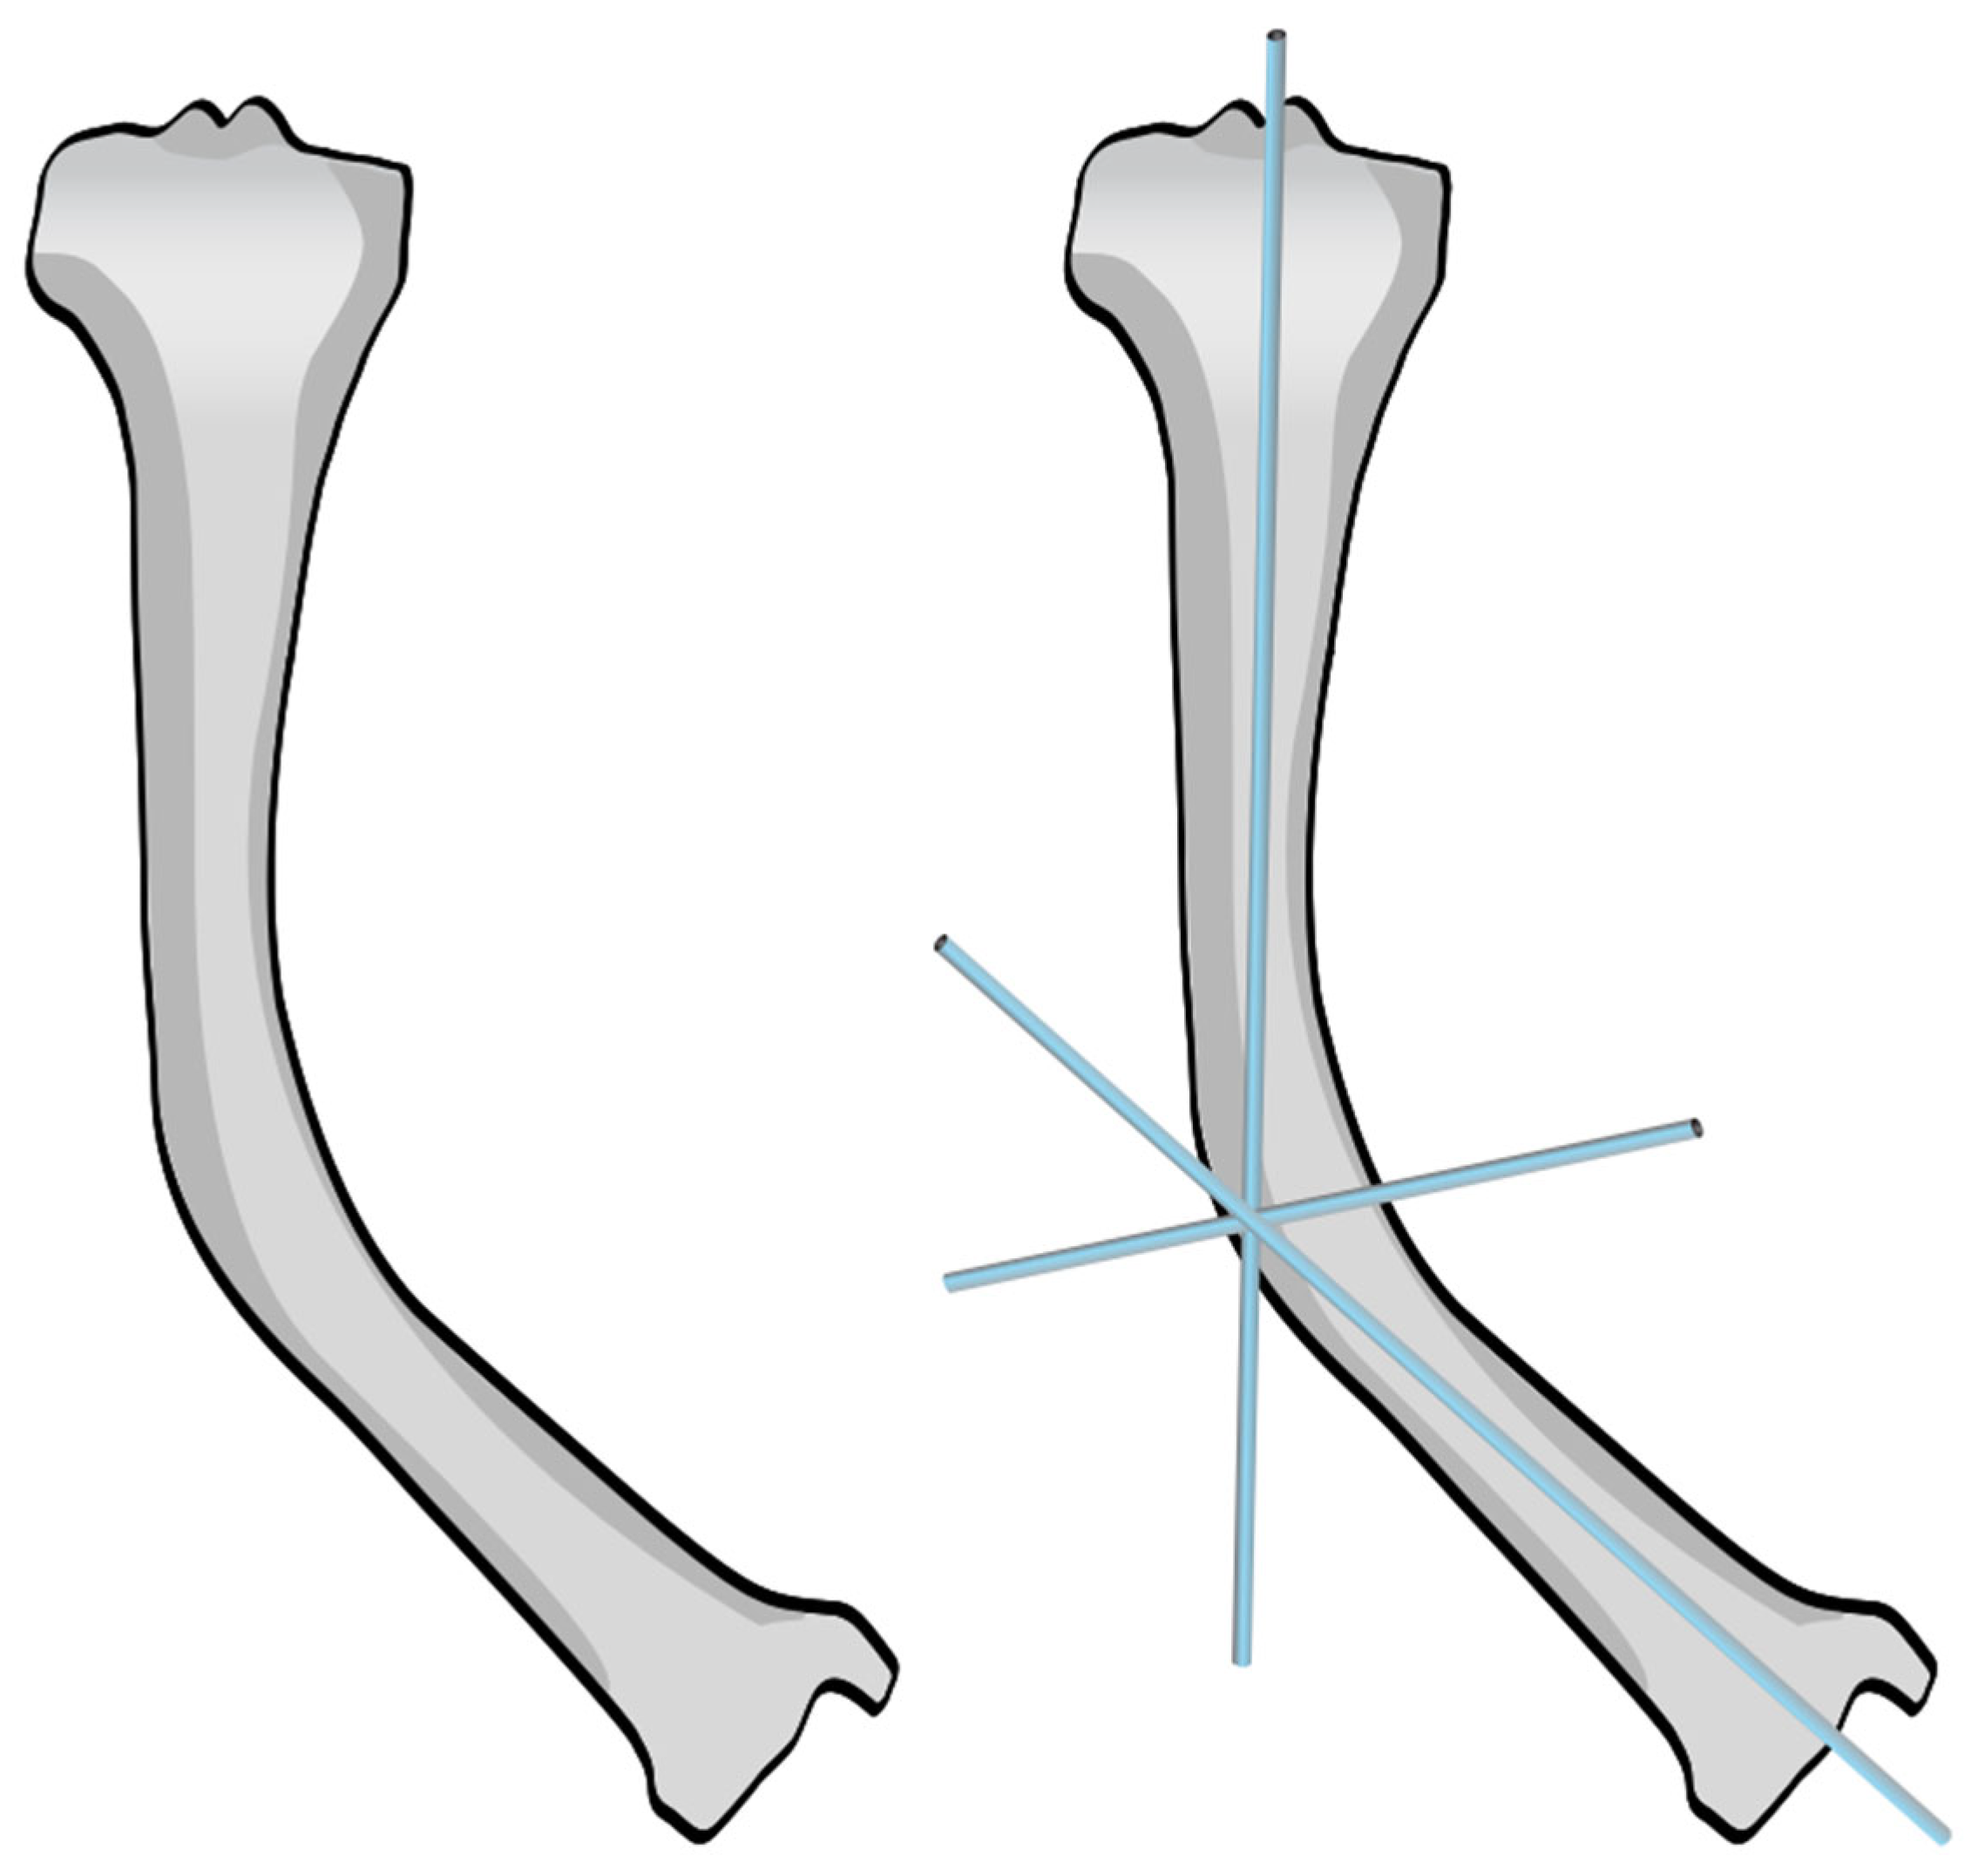

Two options are available: the first one is a straight-cut osteotomy using an oscillating saw, which creates a smooth planar surface on either side (Figure 6a). This method, however, provides minimal rotational stability once the bone segments are reduced (Figure 6b). Furthermore, the thermal injury generated by the power saw may have a negative effect on bone healing at the osteotomy site. To address these limitations, we used a multiple drill hole osteotomy technique, in which closely spaced drill holes are made along the planned osteotomy plane before making the cut (Figure 6c). This results in opposing surfaces being rugged and not smooth (Figure 6d). This interdigitation acts as a mechanical interlock between the bone fragments once reduced, which offers some rotational stability and reduces the need for fixation hardware (Figure 6e).

Figure 6.

Osteotomy techniques. (a,b): Osteotomy using an oscillating saw. (c–e): Osteotomy using multiple drill holes and an osteotome.